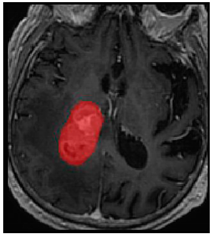

Three cases from the NTUH dataset showing representative results of different models were shown in Table 2, Table 3 and Table 4. The overall dice scores of these networks on the NTUH dataset ranged from 0.33 (DeepMedic) to 0.51 (V-Net). Table 5 shows the detailed performance of each network tested with the NTUH dataset.

Predictions with low dice scores.

Predictions with average dice scores.

Predictions with high dice scores.